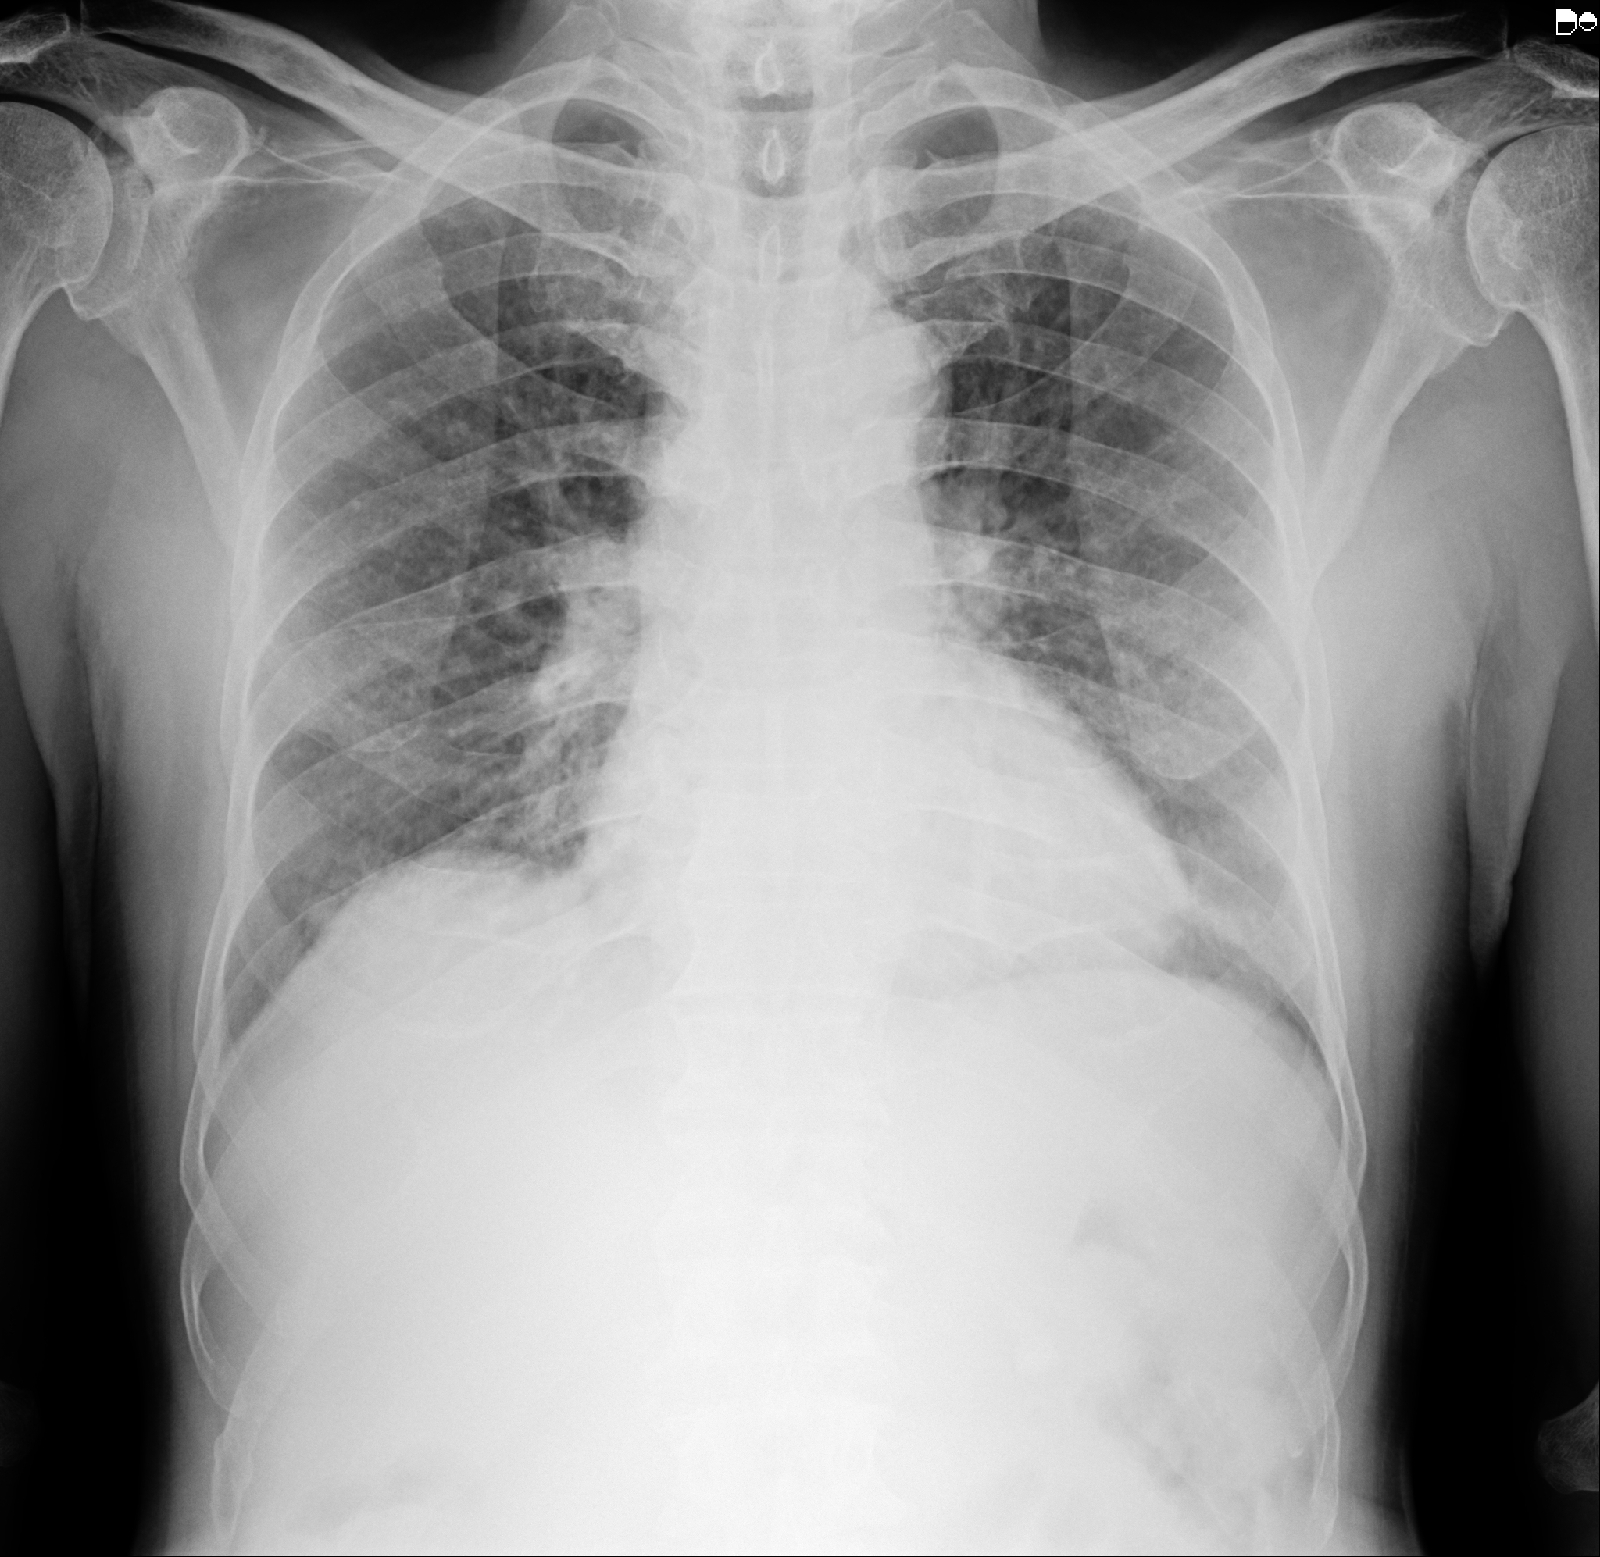

Chest x ray PA view: